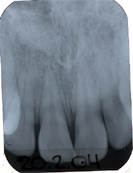

In Abb. 2 ist das Röntgenbild 22 Jahre nach korrekter Wurzelbehandlung mit dem nun überkronten Zahn zu sehen. Der Knochen um die Wurzelspitzen ist entzündungsfrei gesund.

Bemerkung: Da in unseren Breitengraden Zahnwurzelfüllungen seit Jahrzehnten einen weissen Röntgenkontrast machen müssen, können suffiziente und insuffiziente Wurzelfüllungen im Röntgenbild leicht diagnostiziert werden.